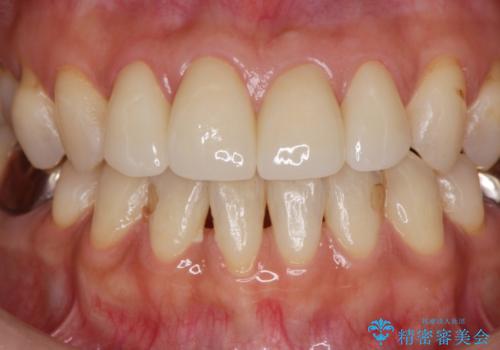

前歯の劣化したコンポジットレジン修復をセラミッククラウンへ

自然な歯の仕上がりに満足いただくことができました。

セラミック治療の注意事項(リスク・副作用など)

- 天然歯を削ります

- 硬い素材は天然歯を傷つけてしまう場合があります

- かみ合わせや歯ぎしりが強すぎる方はセラミックが割れてしまう可能性があります

- 自費診療(保険適用外治療)となります